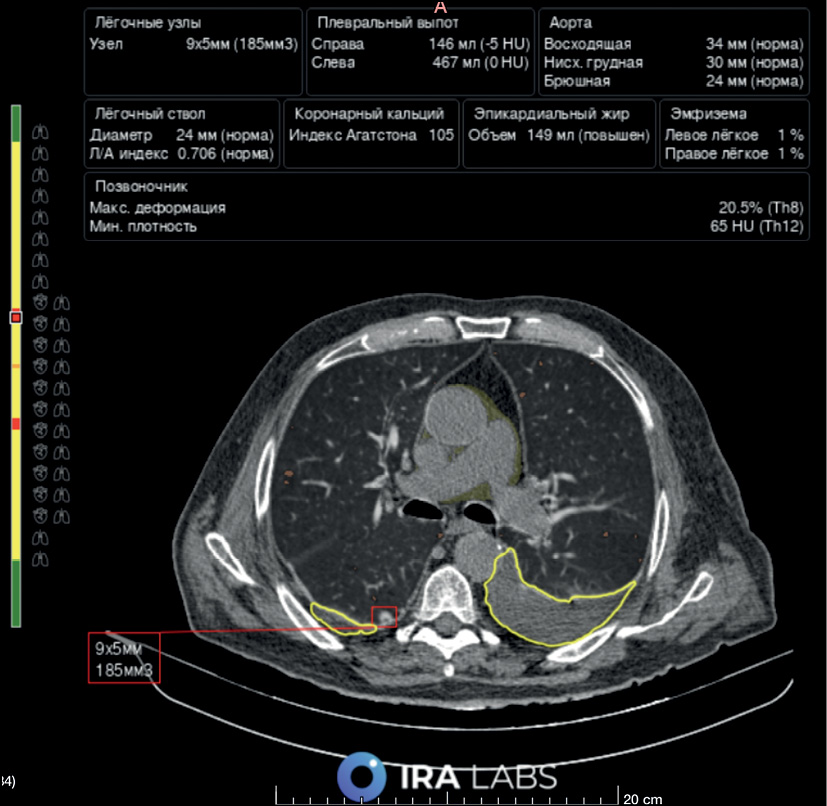

Fig. 6. An example of AI use. Patient B, 76 years old. A radiologist correctly identified bilateral hydrothorax and emphysematous changes but did not describe the lung nodule in the right lung. An AI algorithm revealed all three pathological findings: hydrothorax is highlighted with a yellow line, emphysematous changes are highlighted in orange, and the lung nodule is indicated by a red square.